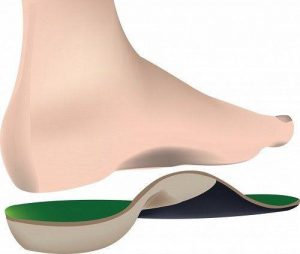

کفی طبی

کفی طبی یا اورتزها، کفیهایی هستند که در کفشها قرار میگیرند تا به اصلاح حالت راه رفتن فرد یا نحوهی قرار گرفتن کف پا روی زمین در هنگام راه رفتن یا دویدن کمک کنند. این کفیها به افراد دچار زانوی ضربدری که یک پایشان بلندتر از پای دیگر است، کمک بسیاری خواهد کرد.